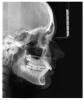

грызунчик Опубликовано 18 сентября, 2009 Автор Поделиться Опубликовано 18 сентября, 2009 пока все, что есть... Ссылка на комментарий

Orthodoc Опубликовано 21 сентября, 2009 Поделиться Опубликовано 21 сентября, 2009 пока все, что есть... Без фотографий, только с рентгеновскими снимками дать совет невозможно. Выкладывайте фотографии. Ссылка на комментарий